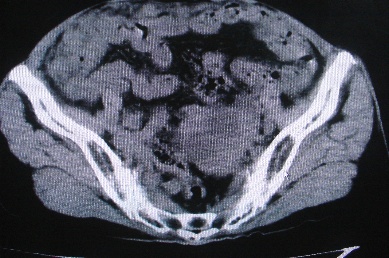

以下是引用卜一在2007-4-30 15:29:00的发言:[br]子宫明显增大,不规则,子宫壁不规则增厚,子宫腔明显缩小,子宫右侧软组织团块与子宫关系密切,内见低密度坏死区。考虑:子宫癌并周围侵润。